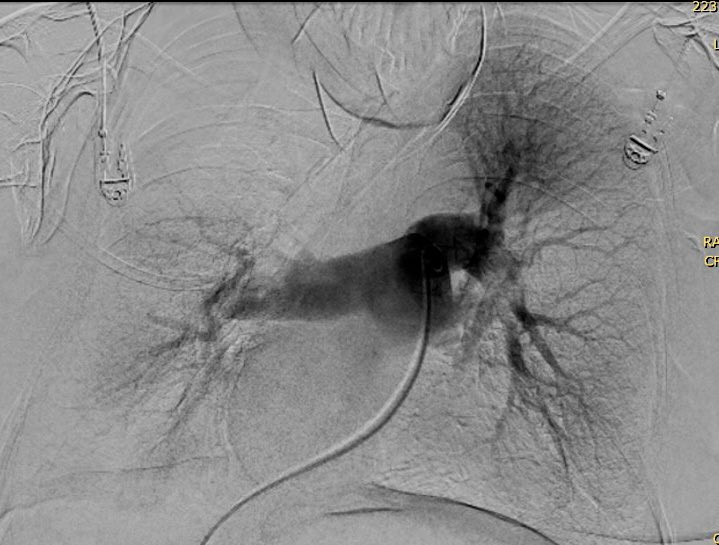

TEP, sistemas de trombectomia, equipos PERT entrenados, Guias de navegación endovascular. Resultados inmediatos. 🇨🇱 Temuco 💪 @HHHATEMUCO @RadiologiaChile @SIDISoc @colmedchile @DrCOlivares @InariMedical @teptips @rduranmendez

Tromboembolismo de arteria pulmonar o TEP. 3era causa de muerte cardiovascular. Araucania con terapia de 1er mundo. Guias de manejo actualizadas. Equipos PERT. Caso de la semana pasada 👌 Mejorando la salud de nuestra población con lo mejor que tiene la medicina, orgulloso

Caso trombectomía aspirativa en #TEP en ⁦@HHHATEMUCO#PE #FLAME #Irad@SIDISoc⁩ ⁦⁦@RadiologiaChile⁩ ⁦@sochimioficial⁩ ⁦@sochimu⁩ ⁦@Sochicaroficial⁩ ⁦⁦@SOCHIVAS_Chile⁩ ⁦@InariMedical#Flowtriever